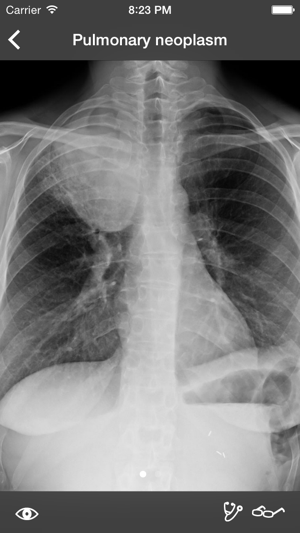

* Now compatible with iOS 8 *RealWorld Radiology is your ultimate guide to the basics of thoracic imaging. Learn to read chest X-rays in no time and discover the most frequent diagnoses through multiple fully annotated examples.RealWorld Radiology currently features more than 70 real-world cases (with more coming for free every month!) each containing: - High-resolution X-rays - All appropriate series (posterioranterior, lateral, expiratory, etc.) - Clinical information regarding the patient and mode of presentation- Detailed radiologic interpretation- Drawings of every radiological finding right on the X-ray Our cases have been especially selected for their high pedagogical value and real-world representativeness. They can be classified either by diagnosis (e.g. pneumonia, atelectasis, pulmonary fibrosis) or by actual radiological finding (e.g. alveolar opacities, interstitial opacities, silhouette sign), making the learning of the differential diagnosis easier than ever while keeping